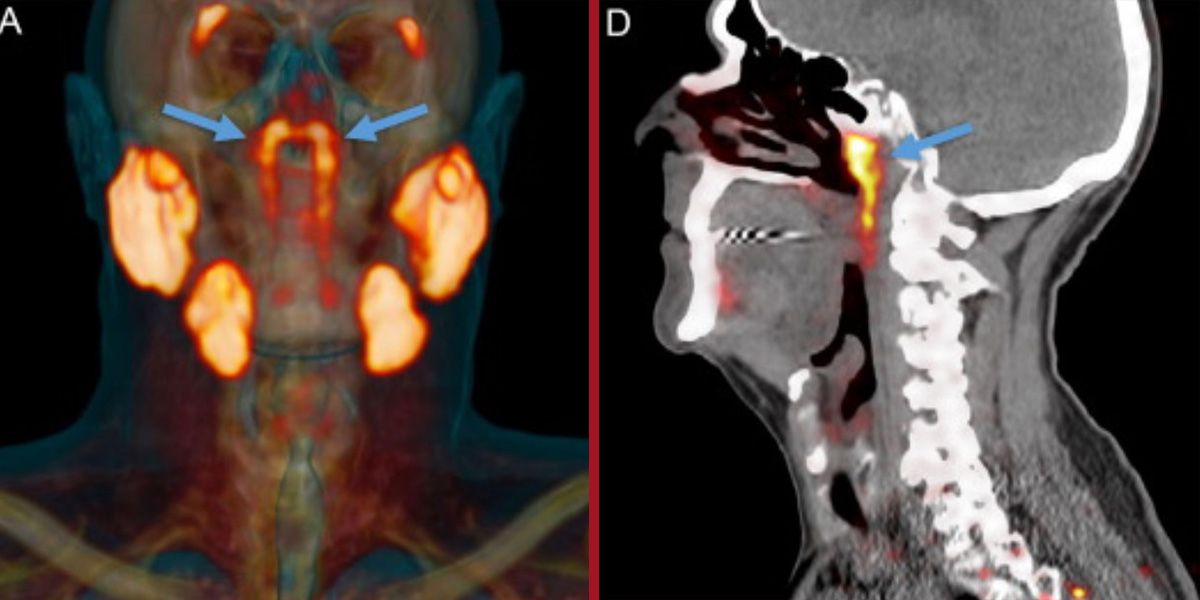

Das Wissenschaftlerteam arbeitete im Netherlands Cancer Institute und führte eine Reihe von CT- und PET-Scans bei Patienten durch, denen radioaktive Glukose (Zuckerlösung) injiziert worden war. Der Grund: Der Zucker würde Tumore auf den Scans zum Leuchten bringen und so leichter erkennbar machen. Es wirkt durch Bindung an das Protein PSMA, das in Prostatakrebszellen häufiger vorkommt. Glücklicherweise ist das PSMA-Protein auch sehr gut für den Nachweis von Speicheldrüsen geeignet. Und siehe da: Bei der Betrachtung der Ergebnisse stellten die Experten fest, dass auch einige Stellen im Inneren des menschlichen Kopfes aufleuchteten.

Bei weiteren Nachforschungen stieß das Team auf die sogenannte "Tubarial-Speicheldrüse" (Tubariusdrüse), die sich hinter der Nase in der Nähe des Übergangs zwischen Nasenhöhle und Rachen befindet. Sie befindet sich im Grunde direkt hinter dem Gesicht und ist knapp vier Zentimeter lang. Die Wissenschaftler wiederholten die Untersuchung bei 100 Patienten, um sicherzugehen, dass es sich dabei nicht um zufällige Ausbildungen handelte – und alle hatten die Tubariusdrüse. Auch ein paar Leichen, die das Team untersuchte, hatten die Drüsen, sodass davon ausgegangen werden kann, dass jeder Mensch sie hat. Es wird angenommen, dass diese speziellen Drüsen dazu da sind, den oberen Hals hinter Nase und Mund zu schmieren.